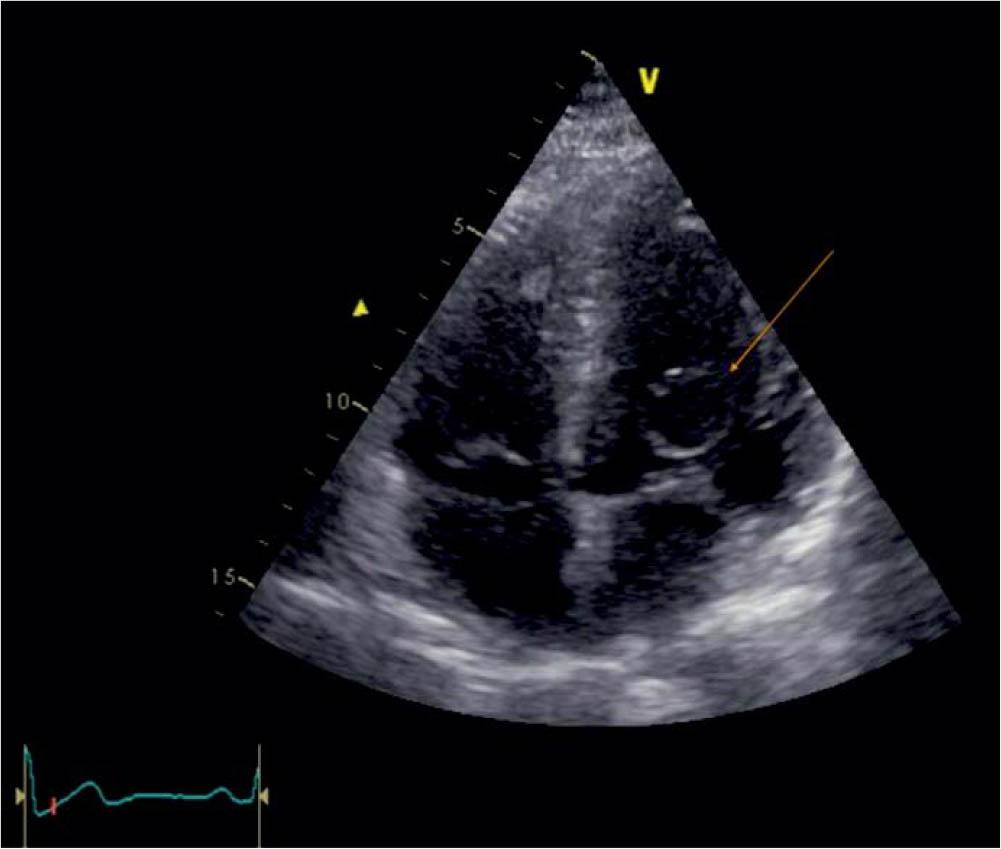

Figure 1

TTE apical 4 chamber, visualization of the blood cyst (arrow) attached to the MV.